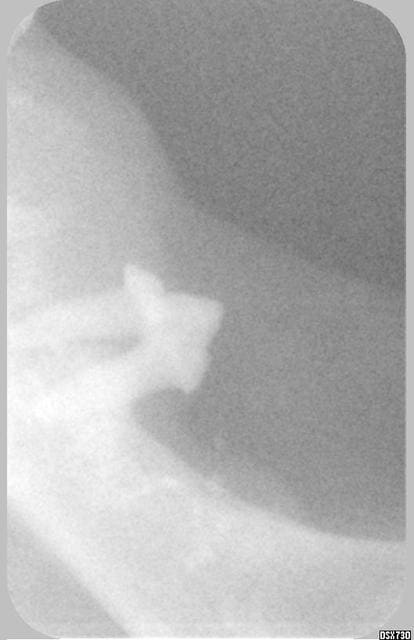

bon ça a marché cette fois ci je ne me souvenais plus comment faire, mes radios dépassaient 200ko.

Effectivement c'était mon chat, la tumeur était trop importante pour être traitée chirurgicalement et la chimio trop lourde pour une chatte de 17 ans passé quand elle n' a plus réussi à s'alimenter j' ai été fort tristement obligée de la faire euthanasier.